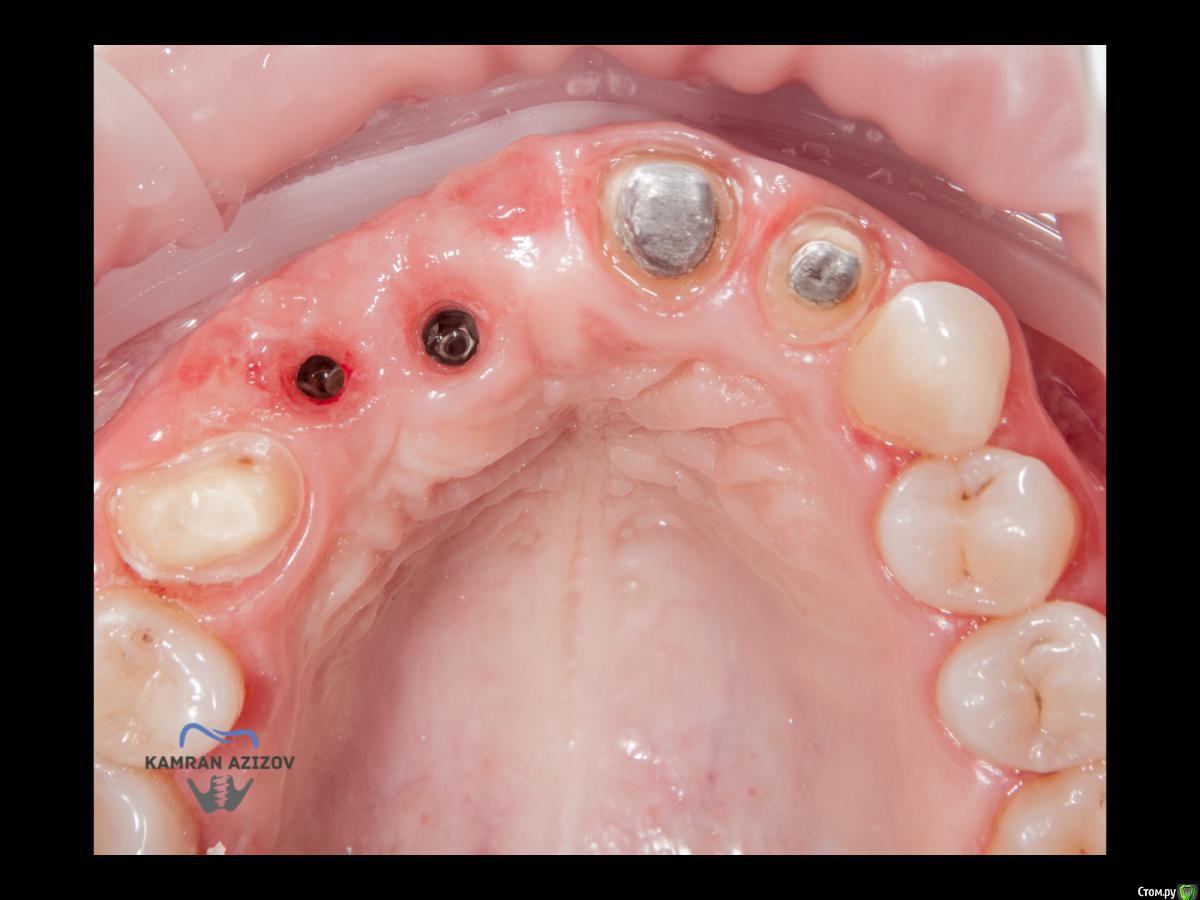

kamranchick Опубликовано 6 апреля, 2019 Поделиться Опубликовано 6 апреля, 2019 (изменено) Хай Гайсдавно ничего не комментировал и не выкладывал, что то настроения не было, да и муза не посещалаСитуация следующаяпришла пациентка, жалобы на неприятный запах из рта, сначала не понял что за хрень, ну как распилил мост понял че к чему... халтура.Ну и по кейсуУдаление клыка и 2ки, через 2 месяца навигация, имплантация + Шашлыки по карлоссу, смена формиков, временное протезирование. только мягкие ткани, Изменено 6 апреля, 2019 пользователем kamranchick 7 1 Ссылка на комментарий

jm3300 Опубликовано 6 апреля, 2019 Поделиться Опубликовано 6 апреля, 2019 А 12- на винтовой? Ссылка на комментарий

kamranchick Опубликовано 7 апреля, 2019 Автор Поделиться Опубликовано 7 апреля, 2019 Тут все на винтовой фиксации Ссылка на комментарий

Дмитрий М Опубликовано 9 апреля, 2019 Поделиться Опубликовано 9 апреля, 2019 kamranchick11з консоль, или это единая конструкция? Ссылка на комментарий

kamranchick Опубликовано 9 апреля, 2019 Автор Поделиться Опубликовано 9 апреля, 2019 kamranchick11з консоль, или это единая конструкция?13-12 с консолью на 11 Ссылка на комментарий